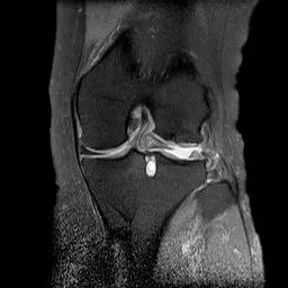

桶柄状撕裂MRI表现

1、宽度减小,在通过半月板体部的冠状面上蝶形消失,同时可见内移的半月板位于髁间窝、交叉韧带旁2、矢状面示残余的前角或后角变小或截断3、半月板前(后)角增宽或双半月板前(后)角征4、双前交叉韧带或双后交叉韧带征

桶柄状撕裂:宽度减小,在通过半月板体部的冠状面上蝶形消失,同时可见内移的半月板位于髁间窝、交叉韧带旁

桶柄状撕裂:半月板后角增宽

半月板撕裂:桶柄状撕裂(双前角征)

桶柄状撕裂(双后交叉韧带征)

桶柄状撕裂:双前交叉韧带征